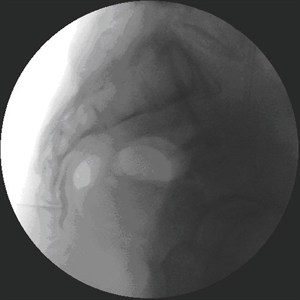

De patiënt moet in buiklig op de behandeltafel gaan liggen. Wanneer de patiënt onder narcose is, zal de arts de naald tot tegen het ganglion van Impar brengen. Hiervoor prikt de arts de naald door het sacro-coccygeaal ligament (= ligament tussen heiligbeen en staartbeen). De arts kontroleert door middel van röntgenstralen en toediening van kontraststof de juiste ligging van de naald voordat het lokaal verdovend middel, het corticoïdpreparaat of de neurolytische oplossing wordt geïnjekteerd.